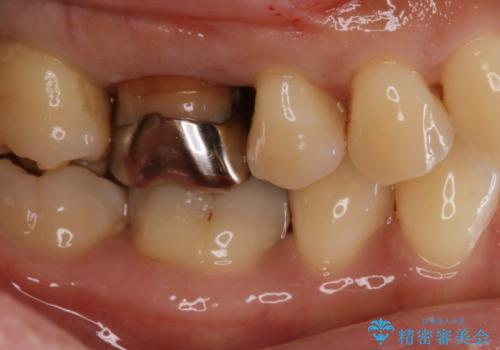

- 右上4、5の歯がしみるのを治したいという主訴で来院されました。精査の結果隣接面う蝕と診断し、適合がよく見ためも良いセラミックインレーでの治療を行いました。

セラミックインレーを入れた後は歯がしみることはなくなり、白く丈夫な被せ物が入り満足いただけました。